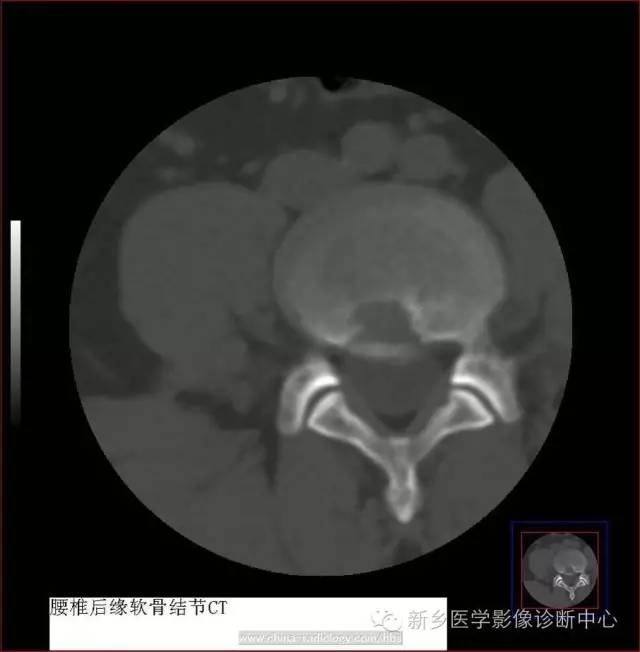

CT表现病变椎体后缘骨质缺损区,多位类圆形或分叶状,大小不一,与同层椎间盘密度相等,CT值为65~90HU,边缘清楚,常有厚薄不一的硬化带,骨质缺损区后方均可见条状或弧状骨块突入椎管内,骨块多与椎体一侧相连,少数两侧与椎体完全分离,可致椎管狭窄、硬膜囊受压。当病变椎体后缘增生硬化非凡明显时,椎体后缘骨质缺损情况需仔细辨认并结合MRI检查以明确诊断。